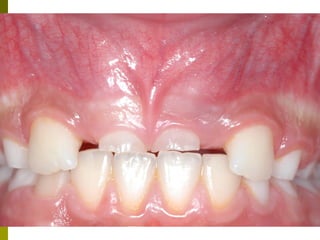

Πρώτη σχολική ηλικία 6-10 ετών

   Αρχίζει αλλαγή των τομέων και η ανατολή των

πρώτων μόνιμων γομφίων (μεικτή οδοντοφυΐα)

   Παρατηρούμε η αλλαγή δοντιών να γίνεται με τη

σωστή σειρά και στη σωστή θέση

   Μπορεί να χρειαστεί πρώιμη ορθοδοντική

θεραπεία, για να αποφευχθούν πιο δύσκολες και

πολύπλοκες εργασίες αργότερα

   Διατήρηση νεογιλών δοντιών στον οδοντικό

φραγμό μέχρι τη φυσιολογική τους απόπτωση